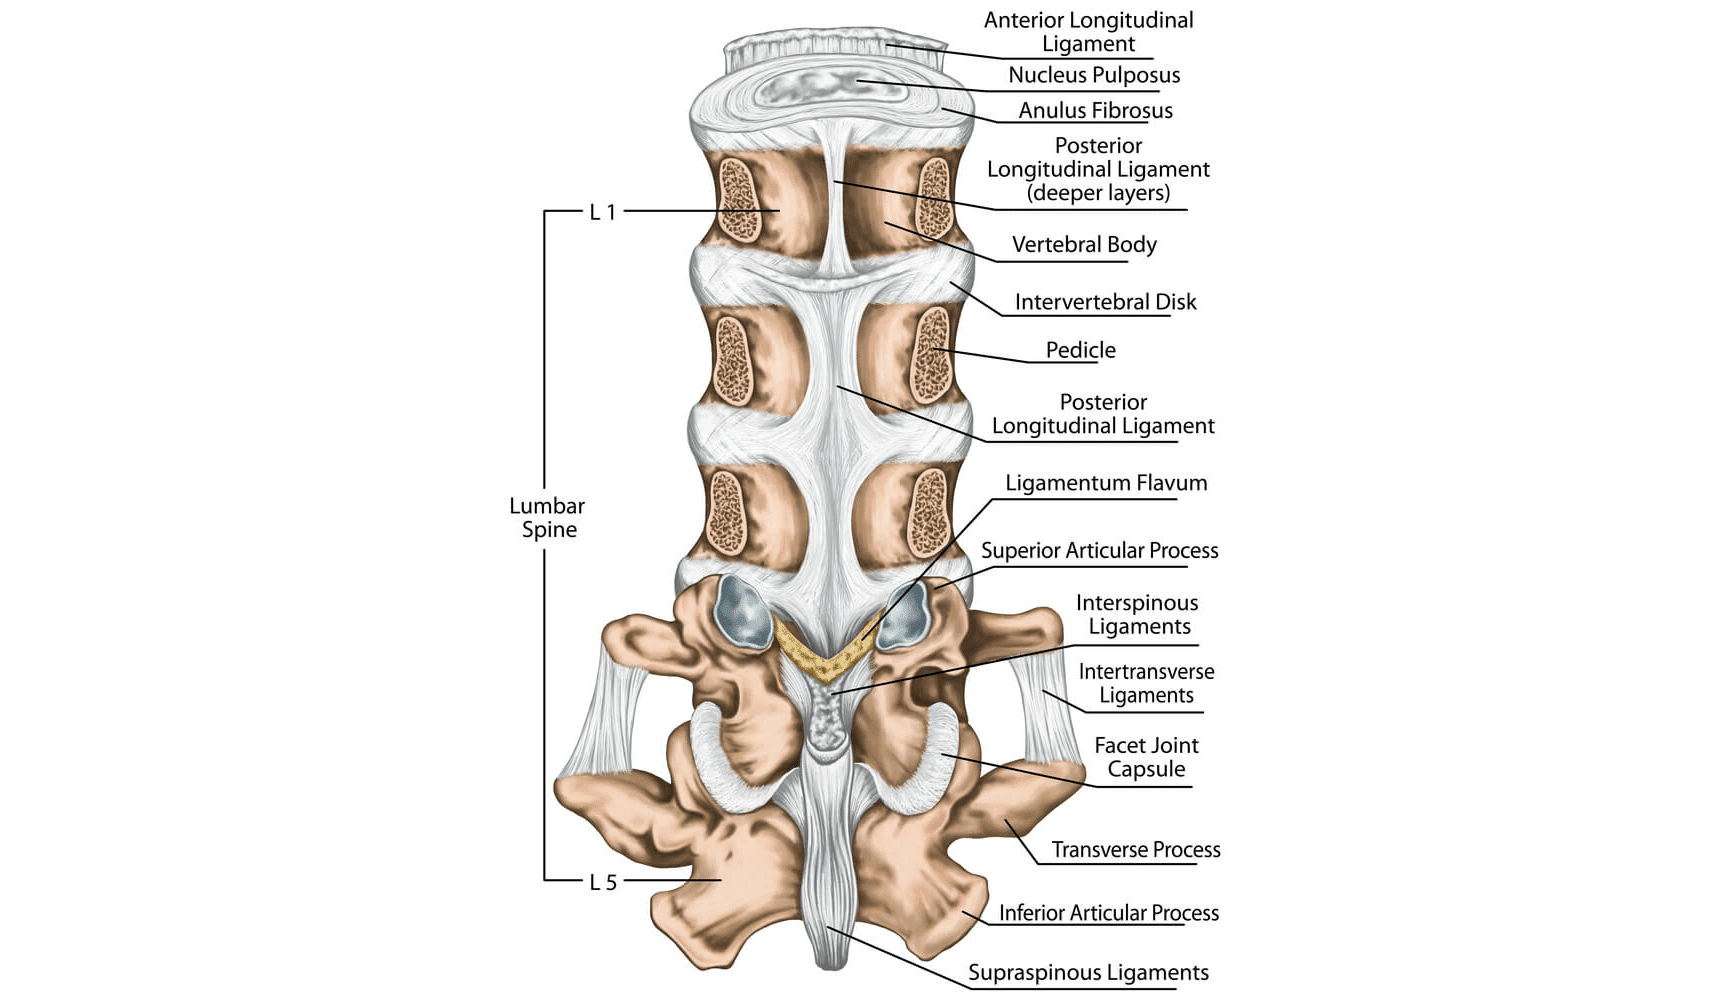

Lumbar Ligament Sprain-degeneration and Prolapsed Lumbar Intervertebral Disc: A Frequent Missed Combination | Cureus

Lumbar instability as an etiology of low back pain and its treatment by prolotherapy: A review - Ross A. Hauser, Danielle Matias, David Woznica, Benjamin Rawlings, Barbara A. Woldin, 2022

Ligaments Lumbar Spine Structure Ligaments Surrounding Lumbar Spine Posterior Longitudinal — Stock Photo © stihii #603749832